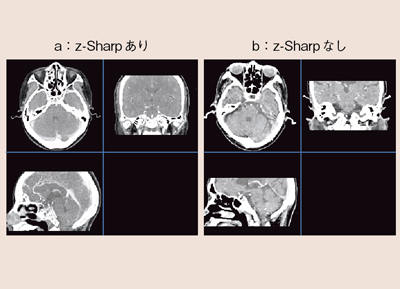

Definition Flashのディテクタ幅は0.6mmであるが,z-Sharpは,1プロジェクションごとにディテクタ幅の半分である0.3mmずつのオーバーサンプリングが特徴である。図1のように,通常のスキャン(図1a)の場合,画像が体軸方向にボケてしまうのに比べ,z-Sharpでオーバーサンプリングすることで,信号値を正確に検出することができ,解像度の高い画像を描出することが可能となる(図1b)。ファントムをコロナル画像として見る検証においても,z-Sharpを使った場合は,CT値が正確に得られていることがわかる(図2b)。さらに,形状の再現性も高い。

図1 z-Sharpの有無による解像度の違い

図2 z-Sharpの有無による空間分解能の違い

図9に,z-Sharpの有無による頭部の画像を示す。Windmillアーチファクトは,アキシャル画像で風車状に現れ,コロナルやサジタルでは,筋状になることが画像の異質感を生む。z-Sharpによりどの方向からでも同一の画質感で観察することができ,解像度の高いボリュームデータを得ることができる。これは,3D画像でも同様である(図10)。ボリュームデータを幅の広い照射野によって得ようとすると,X線ビーム幅が広がることにより,散乱線の影響や,線束中心と辺縁の空間分解能の違い,ヒール効果の影響による画像の劣化が表れてしまう。照射野を広げ過ぎずz-Sharpを用いることで,すべての位置において安定した高いボリュームデータを得ることができる。

図9 頭部におけるWindmillアーチファクトの影響